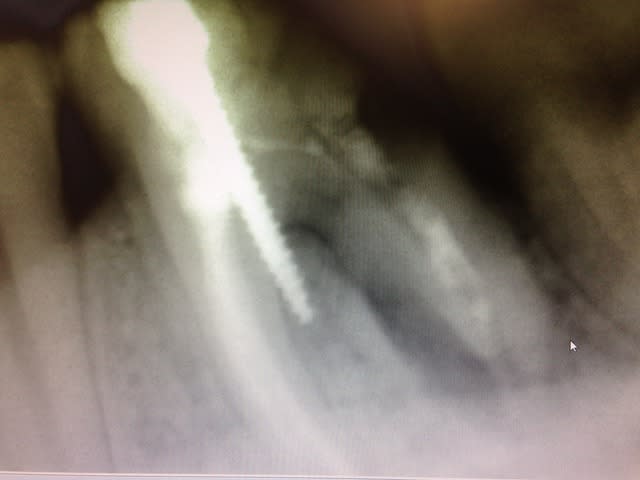

endo ...?

implanto....?

made in france en tout cas

c'est bon les échanges entre pays, on progresse

Img 0186 x9vjj0 - Eugenol

Img 0187 d6lde1 - Eugenol